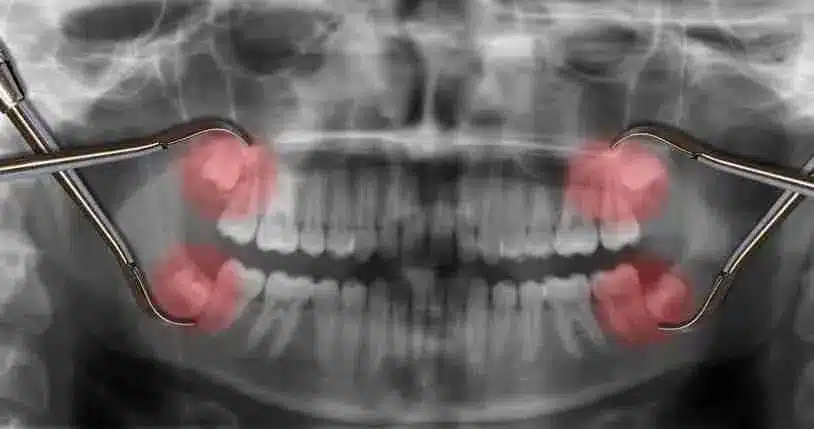

除了蛀牙,智齿 X-ray 检查也是很多年轻人的刚需。很多人的智齿是横着长的,俗称“埋伏牙”,这种牙齿如果不通过牙齿 X-ray 扫描定位,医生很难判断拔牙的难度。对于想要改善美观的朋友来说,牙齿矫正 X-ray 更是必不可少的步骤。它能让医生看清你的骨骼结构,制定最合理的移动方案。

| 全景 X 光 (OPG) | 查看整口牙齿、牙周骨骼和颚骨状况 | 全口检查、智齿评估、初步矫正咨询 |

| 锥状束 CT (CBCT) | 提供 3D 立体影像,精确度最高 | 植牙前 X-ray 检查、复杂口腔外科影像 |

不管是小型的补牙还是大型的口腔手术,影像资料都是核心。比如在计划植牙时,植牙前 X-ray 检查是非常神圣的一步。医生需要通过 3D 扫描确认你牙槽骨的厚度和神经线的具体位置,这直接决定了植牙的成功率和安全性。如果没照清楚就动工,风险是非常大的。